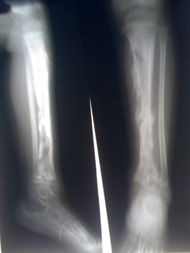

Osteomyelitis of the tibia of a young child. Numerous abscesses in the bone show as radiolucency. | |

التهاب العظام Osteomyelitis مرض يصيب العظم ونِقْيَ العظم، (مادة هلامية في وسط العظام).